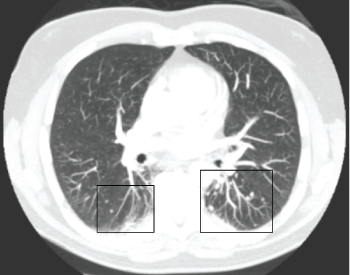

Aged 55 he presented with a Pulmonary Embolus (PE), confirmed on CT Pulmonary Angiography (CTPA). Further CTPA imaging excluded recurrent PE as a cause of escalating shortness of breath symptoms. Radiology review of sequential CT chest imaging (2006-2008) demonstrated multiple pulmonary nodules consistent with Caplan's syndrome (Figure 1). Subsequent development of rheumatoid vasculitis has been treated effectively with rituximab.

Figure 1: Horizontal CT single slice. Black frames highlight multiple well circumscribed > 0.5 cm Caplan's nodules throughout lower lobes bilaterally, more marked on left than right. View Figure 1